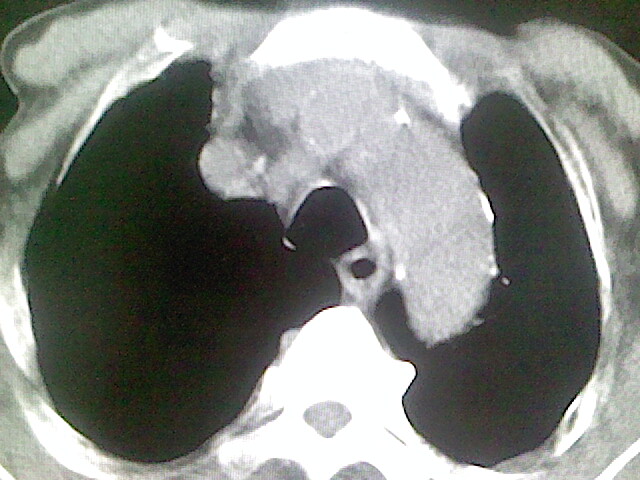

以下是引用zsl6918在2008-8-28 16:49:00的发言:[br]双肺炎性病灶,食管狭窄估计与心房增大压迫所致。

以下是引用xulianj在2008-8-28 20:36:00的发言:[br]慢支肺气肿伴感染,右上肺陈旧性结核;食道建议胃镜检查。

以下是引用wqs571018在2008-8-28 21:18:00的发言:[br]慢支继发感染,右上肺陈旧性结核;食道建议胃镜检查。